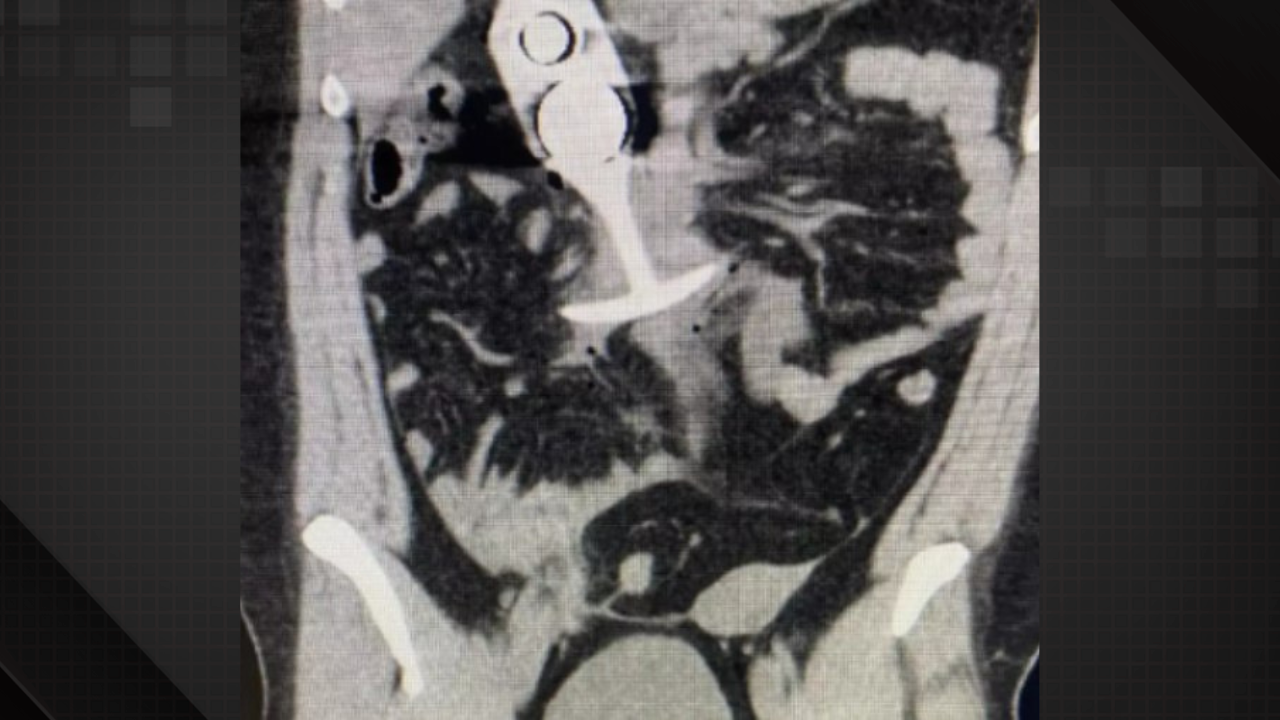

Uma mulher viveu uma situação inusitada ao realizar uma ressonância magnética e descobrir que havia esquecido um brinquedo adulto em seu corpo. O objeto, composto de material metálico, reagiu ao poderoso campo magnético da máquina, provocando complicações médicas inesperadas. Esse incidente reforça a importância de se atentar a orientações prévias ao exame, já que dispositivos metálicos podem representar sérios riscos à saúde durante o procedimento.

O caso ganhou grande repercussão nas redes sociais pela sua natureza curiosa e inesperada, gerando diversos comentários e discussões sobre cuidados com brinquedos adultos e a importância de verificar a presença de objetos metálicos antes de exames médicos. Profissionais de saúde alertam para os perigos envolvidos, destacando que a atração magnética pode causar deslocamentos internos e outros problemas de saúde.